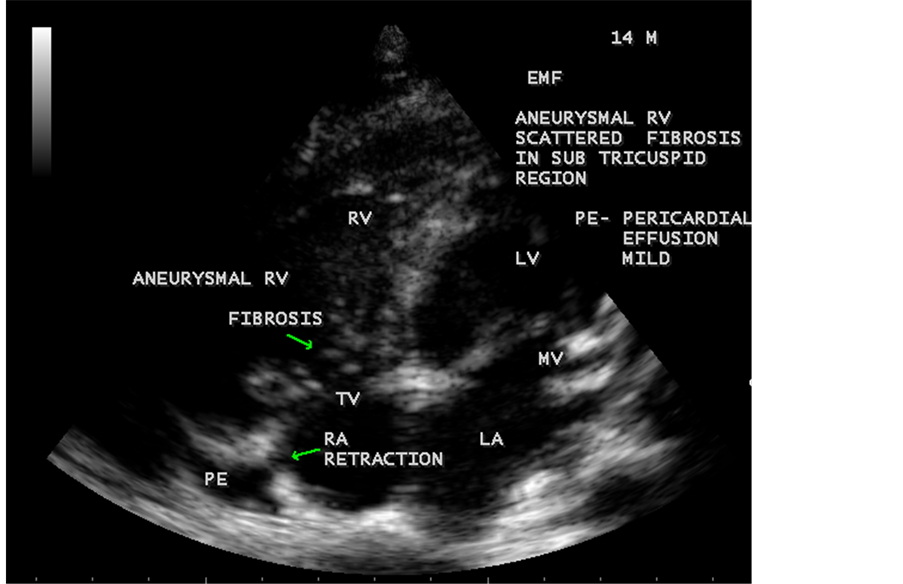

Figure 43. Endomyocardial fibrosis showing subtricuspid fibrosis, aneurysmal right ventricle, mild pericardial effusion and right atrial notch (RA retraction) in a 14-year-old male.

Figure 44. Showing mild pericardial effusion is an initial manifestation of Endomyocardial fibrosis in a 67-year-old male.

Endomyocardial Fibrosis may present as dilated cardiomyopathy in a child as shown in Figure 37 and Figure 38 [34] . In some cases, scattered areas of fibrosis in the submitral and subtricuspid regions (subvalvular fibrosis) as shown in Figure 43 and may cause valvular regurgitation. The valvular regurgitations occur in rheumatic heart disease and the differential features are given in Table 2. It may coexist with RHD (rheumatic heart disease) rarely as shown in Figure 28, Figure 54, Figure 55 and Figure 63 [35] .

Today echocardiography is used as the screening tool at the community level as the diagnosis of EMF could be confirmed at the bedside. Echocardiography accurately assesses the pathological abnormalities of chronic disease and it is the gold standard technique for the diagnosis of EMF [36] . It reveals dense endomyocardial echocardiograms along different parts of the mural and valvular endocardium and AV valve dysfunction [37] as shown in Figure 3 to Figure 7, Figure 10 to Figure 15, Figure 17, Figure 18, Figure 20 to Figure 75 and Figure 78 to Figure 84. The typical feature of EMF is the obliteration of trabecular portion of the ventricle and in advanced cases, there is shrinkage of the cavities creating an apical notch, regurgitation, slow flow with spontaneous echo contrast as in Figure 36 and considerable pericardial effusion. Similar to apical notch of right ventricle, a right atrial notch is well seen as contraction (or retraction) of tricuspid annulus as in Figure 41 and right atrial notch as in Figure 42 and Figure 43, indicating the retraction of right atrial cavity as a peculiar feature of right ventricular EMF. Biventricular enlargement as shown in Figure 41 and biatrial

enlargement as in Figure 33 are the characteristic features of advanced stage of EMF. The fibrosed muscular trabeculae extending into the cavities from the walls of the chambers in the right ventricle visible as “cobra heads” as in Figure 4 and in pericardial sac as in Figure 29. Aneurysmal right ventricle with scattered areas of fibrosis in the sub tricuspid region and a notch in the right atrium is well seen in a 14-year-old boy as in Figure 43. Right atrial notch is frequently noticed in EMF patients as shown in Figure 42 in a 47-year-old male with left ventricular EMF and moderate pericardial effusion.